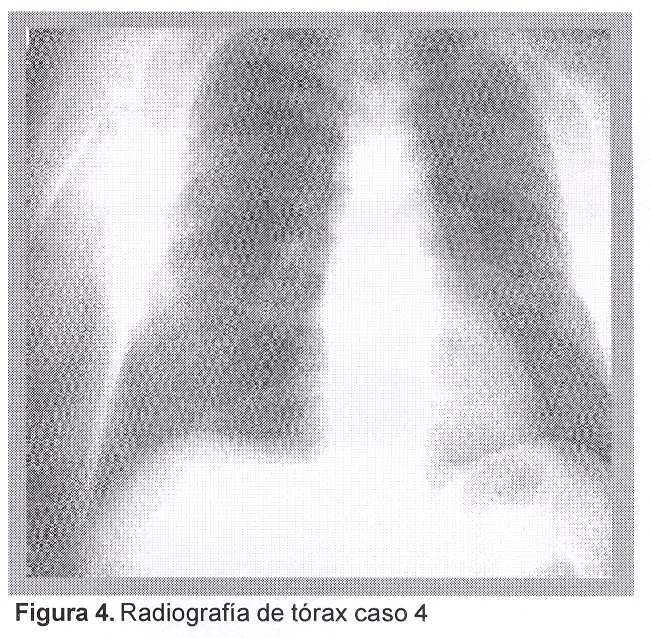

Caso 4. Hombre, 20 años, trabajador procedente de zona rural. Contacto con roedores. Ingresó por fiebre, mialgias, expectoración hemoptoica y disnea progresiva de corta evolución. El examen pleuropulmonar fue normal. Radiografía de tórax: infiltrado reticular difuso (figura 4). Gasometría arterial,VEA: pH=7,45, pCO2=35 mmHg, pO2=84 mmHg, Sa O2=96%, –HCO3=24 mmol/L, BE=–4 mmol/L. Hemograma: glóbulos blancos 20.100/mm3, hemoglobina 10,8 g/dL plaquetas 172.000/mm3. VES=60 mm. Azoemia=0,72 g/L, creatininemia=2,67 mg/dL. Funcional hepático: bilirrubina total 1,68 mg/dL, 0,81 mg/dL, TGO 56 mU/mL, TGP 55 mU/mL. Serología para leptospira, MAT, títulos primera muestra: 1/400. Serovares: Australis/Bratislava, Mini/Mini, Semaranga/Patoc.